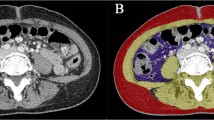

Hospitalized COPD patients were recruited for the assessment of body composition, handgrip strength, respiratory function, and maximal inspiratory and expiratory pressures (MIP and MEP), during hospitalization and 6 months later. Sarcopenia was defined according to the criteria of the European Working Group on Sarcopenia in Older Adults, malnutrition was defined according to French criteria 2007. Survival data were collected 12 months after hospitalization.